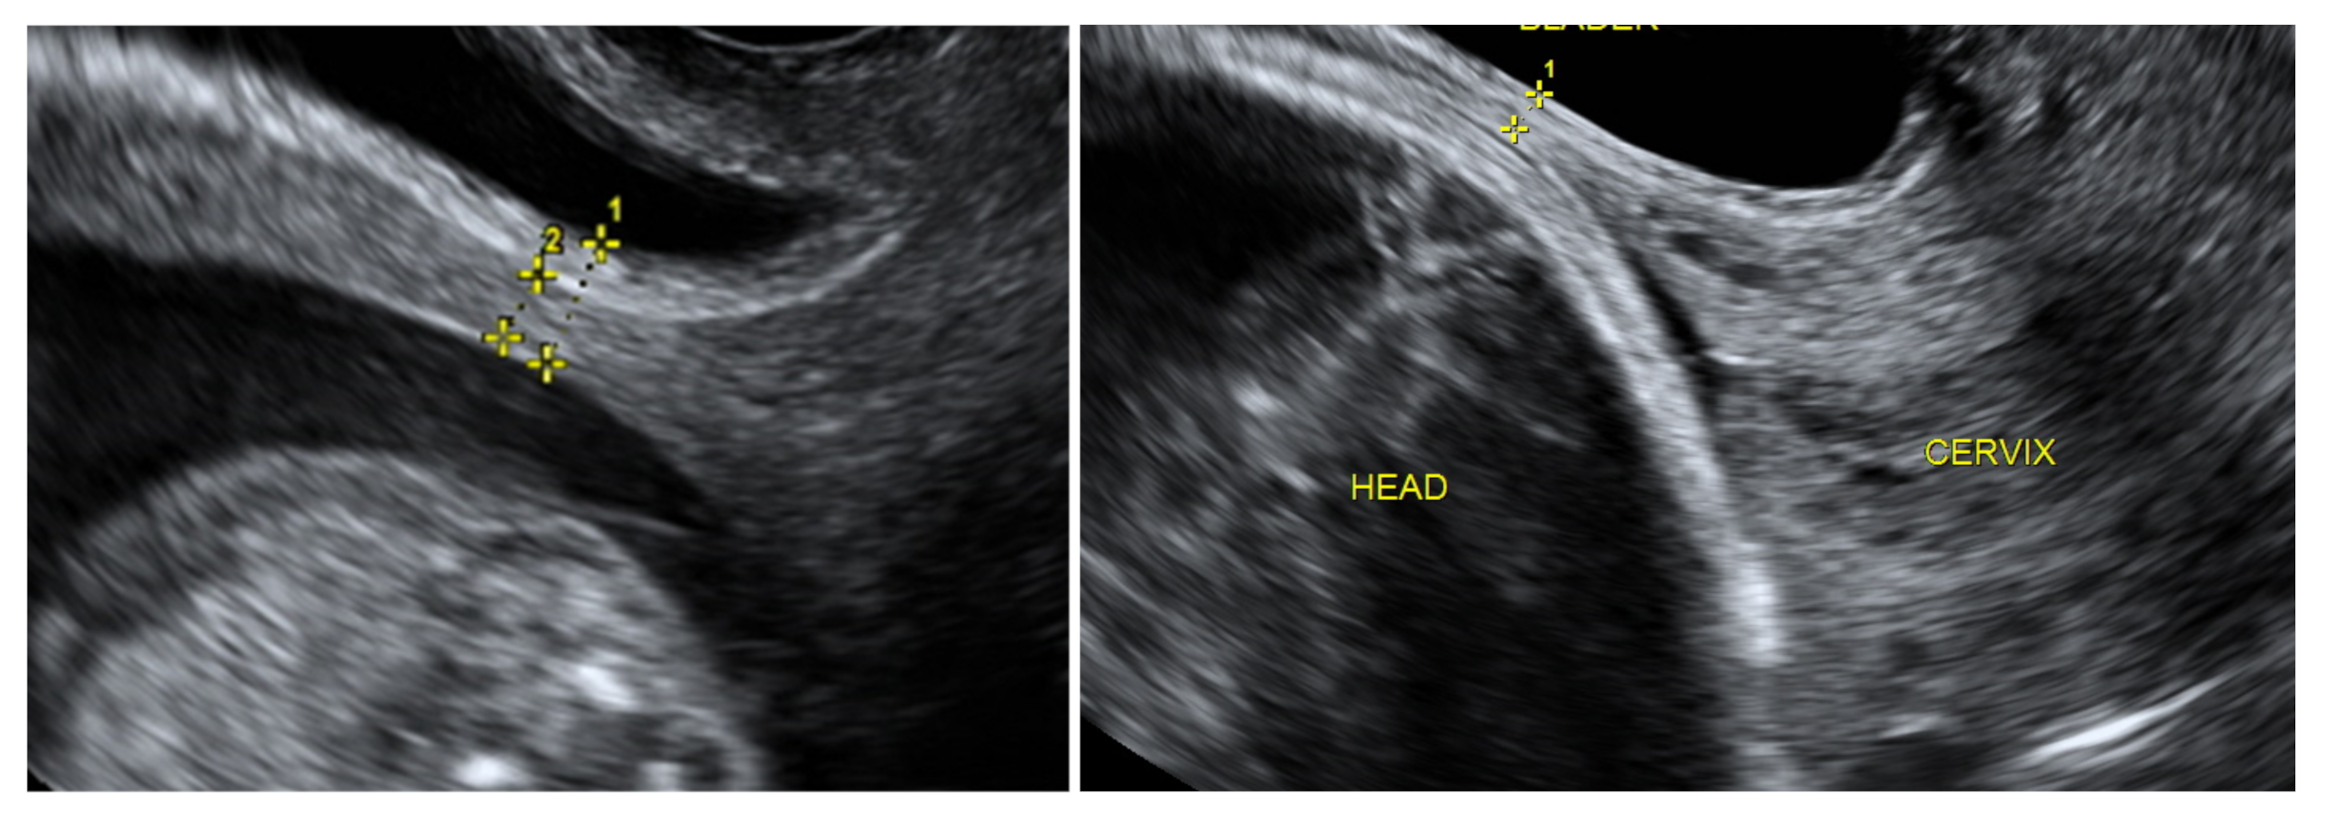

Women over 18 with a singleton pregnancy after at least one previous low-transverse CS and at least twelve months after the last CS were recruited at the 11+0–13+6 week ultrasound screening after the procedures had been explained to them fully. Written informed consent was obtained from all participants and transvaginal ultrasound was performed for a uterine scar examination using a Voluson E8 Expert device (GE Healthcare Ultrasound Korea, Ltd., Seongnam-Si, Korea) with a 4–9 MHz probe. The standardised plane for a CS scar evaluation was performed as a midsagittal view of the uterine isthmus and internal cervical os. CS scar niche was defined as an anechoic area with at least 2 mm depth at the scar site. According to sonographic findings, the study participants were assigned subjectively to the CS scar niche group (niche group) or to the CS scar without niche group (non-niche group). In the CS scar niche group, RMT (distance from the serosal surface of the uterus to the apex of the niche) was measured and presented as CS scar myometrial thickness in the first trimester (Figure 1). The myometrial thickness at the internal cervical os was measured in the non-niche group (Figure 1). Participants needed to have their bladder empty during transvaginal sonography (TVS) in the first trimester. Demographic and obstetric history was obtained during the first scan visit. Second ultrasound examination at 18+0–20+0 weeks and a third at 32+0–35+6 weeks were planned. TVS on a full bladder was used to measure the full LUS and myometrial thickness to delineate the scar area clearly, as was previously described [5] (Figure 2). LUS is a two-layer structure with a hyperechogenic layer, including the bladder wall and a hypoechogenic layer that is considered to represent the myometrium [5] (Figure 2). At least three measurements were taken, with the lowest value being retained. The same investigator was the first researcher (S.E.) and performed all scans as the same ultrasound examination method was applied for CS scar evaluation. All representative images were stored on the local hospital image storage system (MEDDREAM-172.27.1.146). Data were recorded prospectively on an SPSS spreadsheet. Data about pregnancy outcomes and complications were retrieved from an electronic hospital database.

Figure 2. The full low uterine segment thickness (1) (one caliper is placed at the interface between urine and the bladder wall, another is placed at the interface between amniotic fluid (or fetal scalp) and the deciduas); Myometrial LUS thickness (2) (one caliper at the interface of the bladder wall and the myometrium, so includes only hypoechogenic layer) at the second trimester of pregnancy (on the left); and full LUS thickness (1) at the third trimester of pregnancy (on the right), measured by transvaginal ultrasound.